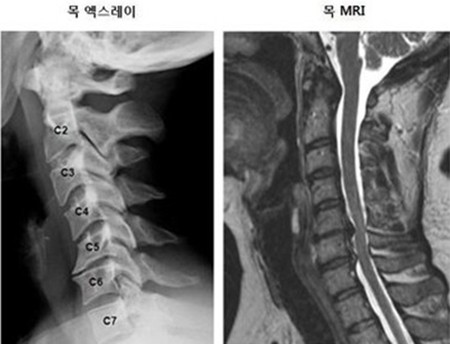

목 디스크는 목의 디스크(경추 디스크)에서 출현하는 질환으로, 경추 디스크 사이의 연골판이 터져 디스크 내부 물질이 경추 신경을 자극해 통증이나 저림증 등의 증상을 유발 해요. 목 디스크는 일상생활에서의 안 좋은 자세나 많은 운동, 부상 등이 이유가 되는 것이 될 수 있기도하고, 시간이 지날수록 발생 확률이 높아져요. 목 디스크의 증상으로는 목 부위의 통증, 팔의 저림, 근육 약화 등이 있으며, 증상이 난폭한 경우 수술 등의 치료가 필요할 수 있어요. 그리하나 대개의 경우 치료 없이도 시간이 지나면 증상이 호전되는 경우가 대부분입니다.

목디스크 증상 첫번째 목 통증이예요. 목이 뻣뻣한 느낌이 들고 움직였을 때 통증이과도하게 느껴지는 경우가 생기며, 이로인해 머리를 돌리기가 어려워 지다고 해요. 이런 목 통증은 목 디스크의 대표적 증상 중 1개라고 하니 참고 부탁드리도록 할게요.

목디스크 증상 목 자세이고요. 현대인들은 스마트폰이나 모니터를 많이 사용하다보니 목이 앞쪽으로 당겨져있는 것처럼 자세를 많이 취하게 된다 하였습니다. 이런 자세는 정상적인 목뼈를 전환 시켜 여러분이 아시는 거묵목 증상이 나타나게 되는 이유가 되는 것입니다.

목디스크가 생겨나게 보면 어깨에서부터 팔을 지나 엄지손가락까지 저리고 아프게 되면서 7번과 8번 신경이 눌려지게 되어 손과 손가락 마디마디가 저리고 통증이 있고요. 이 통증이 팔, 어깨에서 손 및 손가락 등으로 방사하게 되고 있는데 이때 신경 분포에 따라서 대부분 5번 신경이 눌리게 되면서 어깨가 아프고, 6번 신경까지 눌리게 되면서 통증은 더 심해진다고 하더라고요.